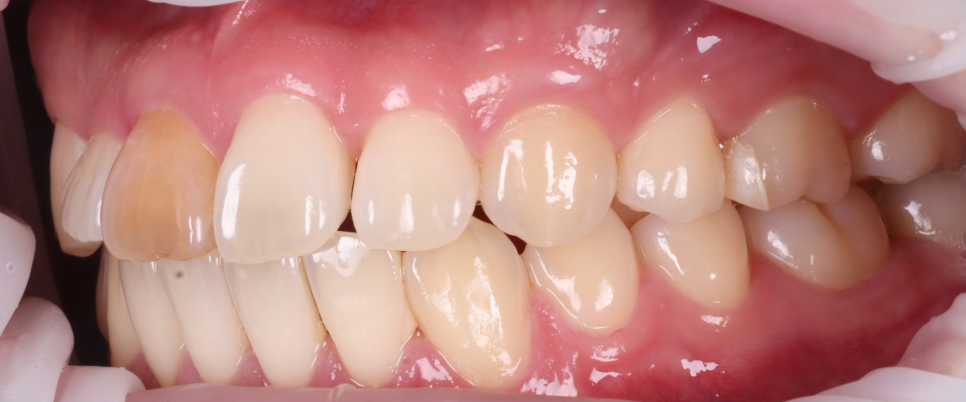

감사하게도 저희 치과에는 꾸준히 치과의사 선생님들의 소개로 타 지역에서 오시는 분들이 참 많은데요. 오늘은 5년 동안 14개의 치과를 다녔지만 원하는 진단을 받지 못해 치료를 포기해야 하나 생각하시던 분의 스토리를 들려드리려고 합니다. 사진부터 보여드릴게요. 촬영일 : 2...

오래전, 외상으로 인해

신경이 죽으면서 앞니가 심하게

변색되었는데요.

타치과에서는

이렇게 진단받으셨다고 합니다.

미백

현재 뿌리가 짧고

신경치료가 완전한 상태가

아니라서 추천X

시술 후 교정 후 유지 장치

연결 불가

균형을 위해 3개의 치아를

깎아서 만들어야 하는데

나머지 치아들이 아까움

뿌리가 짧고

양옆 치아 뿌리의 간섭으로

어려움

➡️ 결론 : 레진 페이징